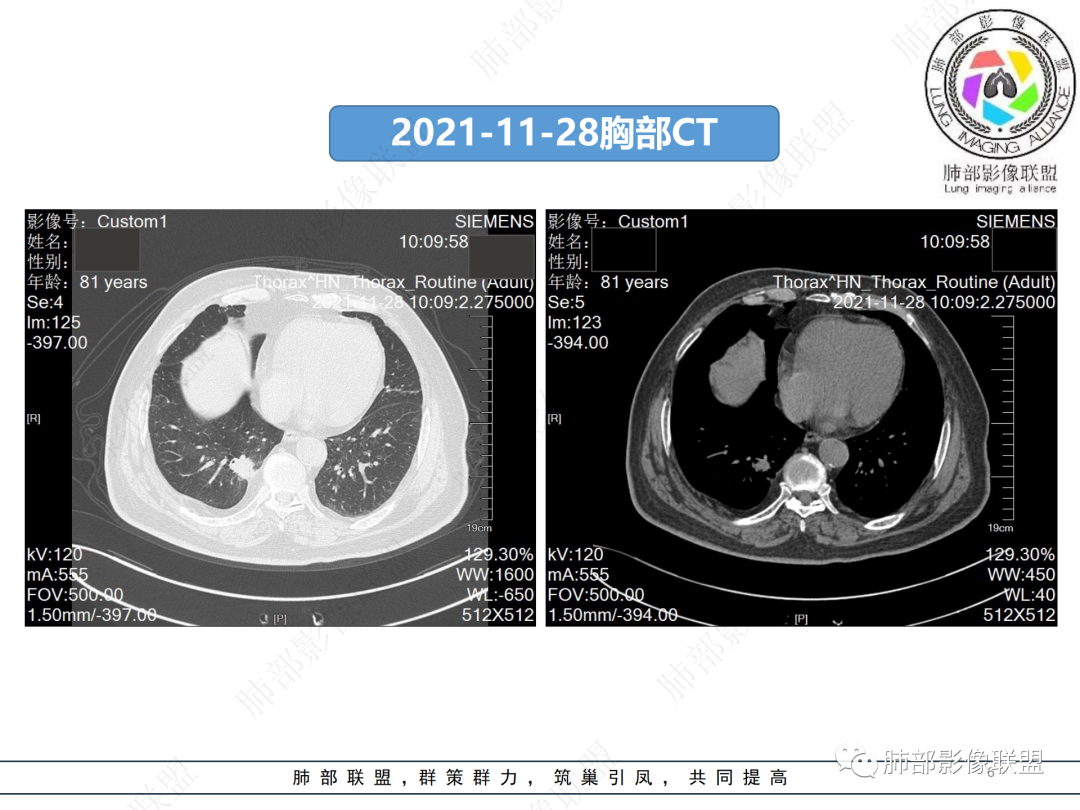

男,81,咳嗽伴痰中带血5天。胸部CT:右肺下叶胸膜下实性结节,边缘毛糙、索条,平直为主,点状钙化,支气管进入病灶边缘并狭窄,邻近胸膜增厚、有牵拉。胸膜外脂肪间隙增宽。平扫内可见点状低密度,强化明显,可见环状强化。考虑慢性炎性肉芽肿,TB?鉴别Ca。

2.右肺下叶后基底段胸膜下不规则结节影,边界清楚多平直,未见典型分叶及毛刺,未见磨玻璃晕影,相邻胸膜增厚轻度收缩。

3.病灶密度较高,前份见钙化结节,未见低密度液化或空洞。不均匀强化且有延迟。后段支气管旁出,未见阻塞。灶周显示条索影,未见明确卫星灶。

4.右侧胸腔少量积液,沿胸膜未见强化小结节影。